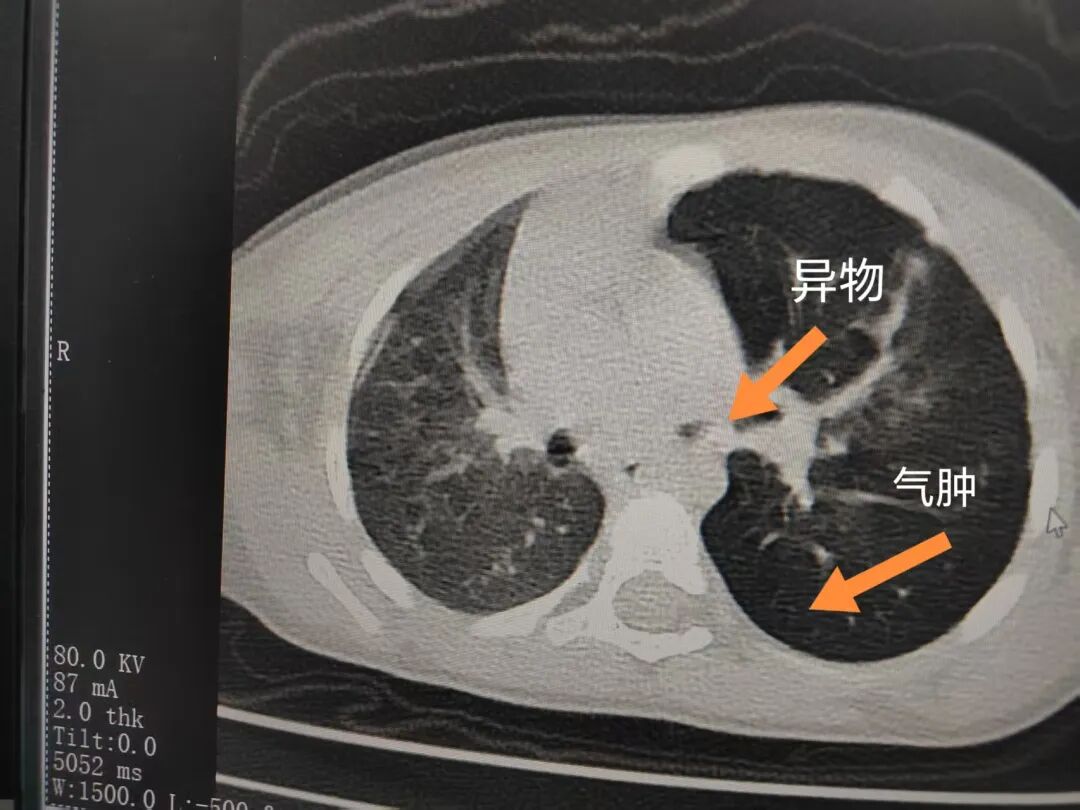

三天后(11月13日),趙寶出現(xiàn)高熱、咳喘加重,家長(zhǎng)著急了,再次帶他來(lái)到醫(yī)院。CT檢查顯示左肺過度充氣,左肺上下葉支氣管主干見不規(guī)則高密度影,左肺上葉可見大片狀密度增高影,縱隔窗實(shí)變,提示為“左側(cè)支氣管內(nèi)異物并繼發(fā)性改變,左肺上葉舌段肺膨脹不全”。

市二院小兒呼吸內(nèi)科副主任楊亞娟介紹,異物誤入氣道可能導(dǎo)致氣道阻塞,嚴(yán)重時(shí)可引發(fā)窒息,甚至危及生命。若異物進(jìn)入支氣管,造成不完全堵塞,可引起阻塞性肺氣腫;如完全堵塞支氣管,則可能導(dǎo)致肺組織萎縮,形成肺不張。此外,若異物存留時(shí)間較長(zhǎng),或?yàn)橹参镄援愇?,容易合并?xì)菌感染,產(chǎn)生膿性分泌物,進(jìn)而發(fā)展為肺炎。她強(qiáng)調(diào),盡早診斷并取出異物,是減少并發(fā)癥、降低病死率的關(guān)鍵。